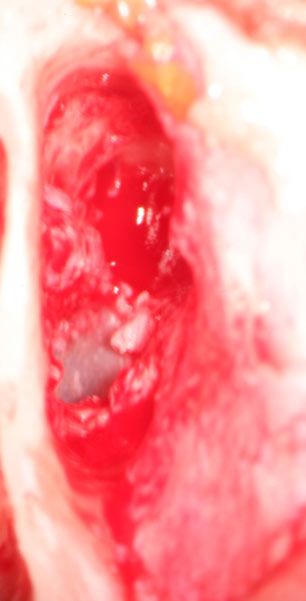

Fotos prä- und postoperativ nach Ohrmuschelkorrektur